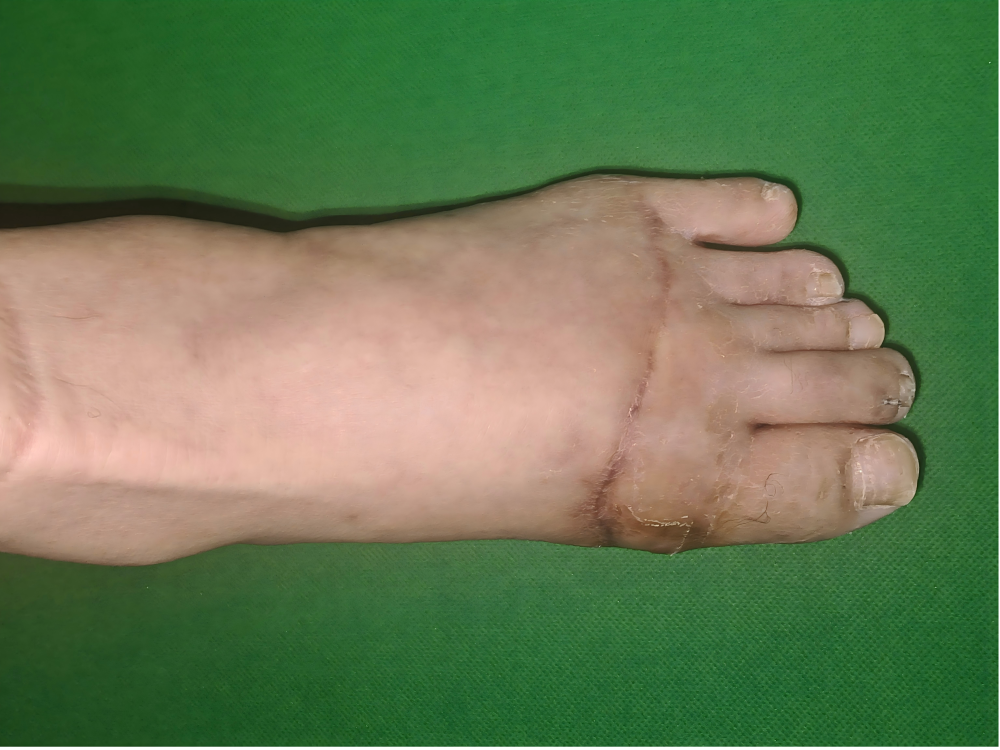

术后,护理团队精心照护、细心换药、指导康复,从帮着活动脚趾到慢慢练习站立,一步步陪着患者恢复。如今,王师傅已经能稳稳地站起来,重新找回了站立与行走的力量。

二、三次手术!绞碎的右上肢“起死回生”